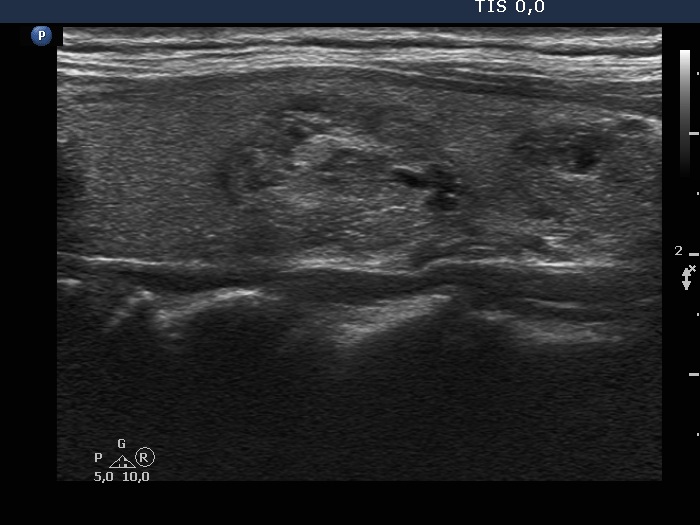

Ultrasonography. The thyroid was echonormal and had multiple moderately hypoechoic and hyperechoic nodules which showed various degrees of cystic degeneration. The largest nodule in the right lobe was dominantly cystic and presented with minimally hypoechoic solid part which included hyperechoic figures. The largest nodule in the left lobe had irregular margins.

2.5 mL cystic fluid was aspirated from the right nodule. Thereafter, the borders became irregular, lobulated. Aspiration cytology of the solid part after the removal of cystic fluid an that of the nodule having irregular borders in the left lobe resulted in bening cystic degeneration.

The left nodule had irregular borders.

The nodule' borders became irregular after aspiration of cystic fluid. This is a phenomenon which should not be regarded as a pathological finding.